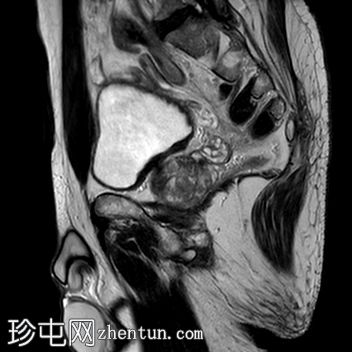

矢状位

T2加权像

前列腺增大,大小为52 x 56 x 57 mm(体积87 ml)。

PSA 7.279 ng/ml,PSA密度0.084 ng/ml/cc。

在前列腺中部/尖部,右侧外周带/周围膜交界处可见一大小为7 x 5 mm的毛刺状、边界不清的T2低信号病灶,伴有扩散受限和早期动脉期强化,提示为PI-RADS 4级病灶。

边界清晰的T2高信号结节,典型良性增生,在移行区(TZ)最大直径达18 mm,符合PI-RADS 1级。

基底部向膀胱内突出。